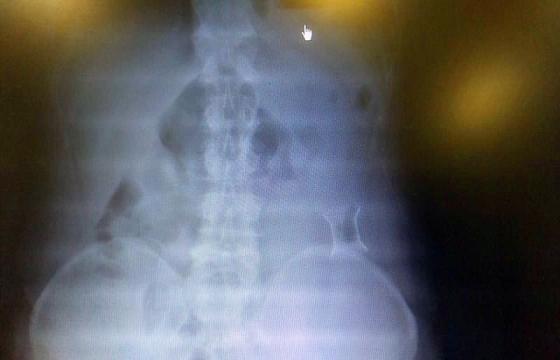

受試患者在結(jié)腸端端吻合術(shù)中,使用我司新研制產(chǎn)品達(dá)到了理想的預(yù)期效果?;颊咝g(shù)后7天、14天X光片顯影,可降解腸道支架均能按研制設(shè)計(jì)的預(yù)期時(shí)間節(jié)點(diǎn)保持應(yīng)有強(qiáng)度,術(shù)后21天X光片顯示可降解腸道支架已完全破碎,并排出體外。在整個(gè)試驗(yàn)過(guò)程中,病患無(wú)任何不良反映,耐受良好。